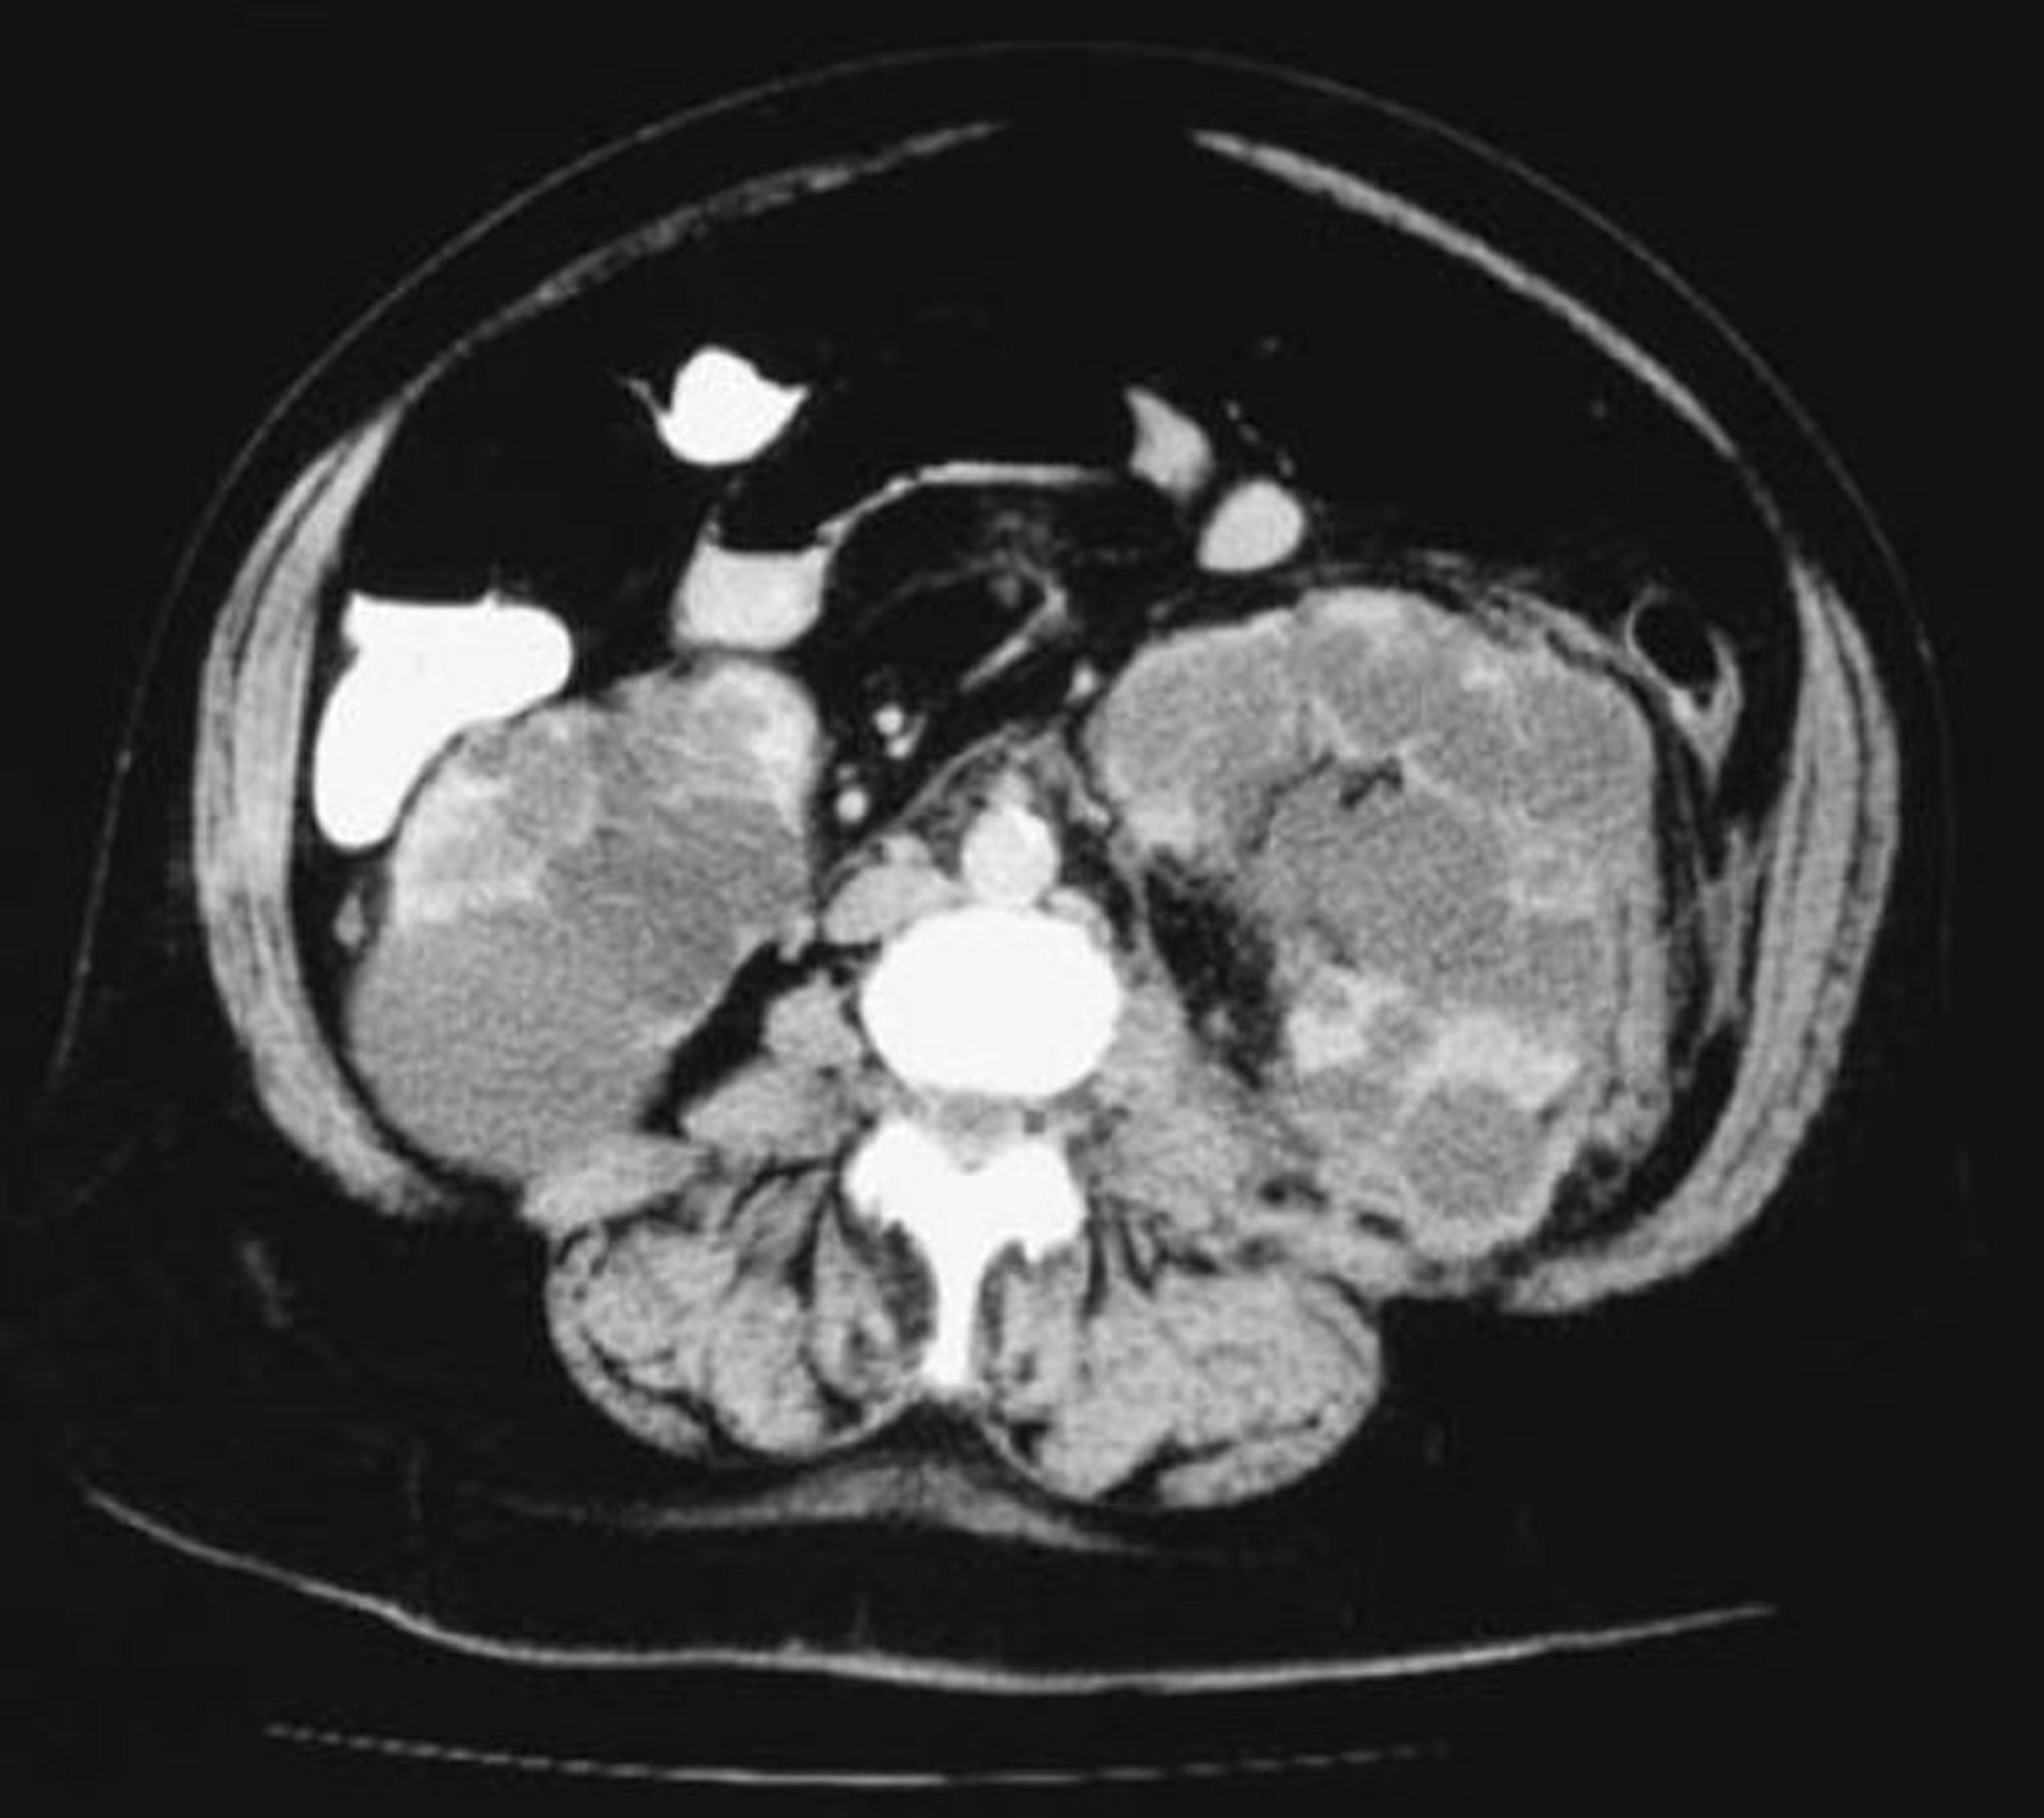

Diagnosis is usually by imaging, showing extensive and bilateral cystic changes throughout the kidneys, which are typically enlarged and have a moth-eaten appearance due to cysts that displace functional tissue. These changes develop with age and are less often present or obvious in younger patients.

Ultrasound is usually done first. For patients with family history of ADPKD, ultrasound criteria (based on age and number of renal cysts) are used to diagnose or exclude ADPKD. Imaging criteria are not established in patients with negative or unknown history. CT or MRI are often done after establishing the diagnosis of ADPKD. CT and MRI are more sensitive than ultrasound in detecting cysts and can be useful in equivocal cases and for measuring cyst and kidney volume, which can have prognostic implications.